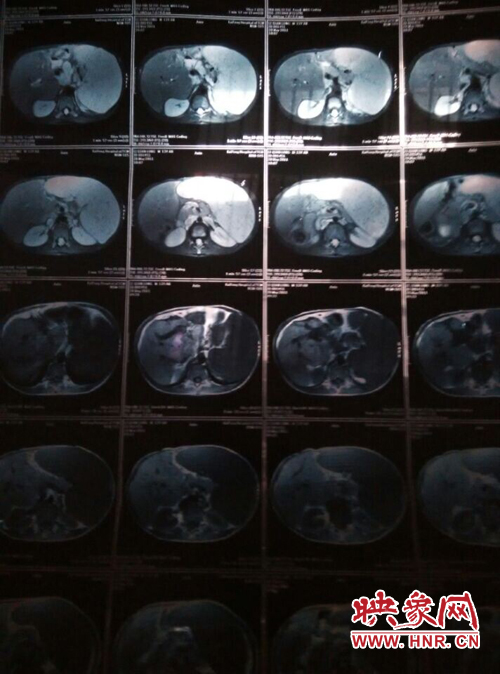

映象網(wǎng)商丘訊(記者 曾巖 代艷)他是一個花季少年,兩歲半時患上怪病,經(jīng)過漫長的求醫(yī)之路查出是肝脾腫大,十幾年的看病之路,花了幾十萬,非但沒有醫(yī)好他的病,讓這個原本就貧困的家庭雪上加霜。

他叫李乾龍,今年16歲,家住寧陵縣城郊鄉(xiāng)李莊村,家里有四口人,目前在寧陵縣黨校就讀上高一,他一邊上學(xué)一邊看病,十幾年來,他們跑遍了大小醫(yī)院,卻一直沒查出他的病因。16歲的他發(fā)育的還沒有13歲的弟弟高,肚子大的像個皮球,經(jīng)常身體發(fā)熱,全身無力,因為沒錢去大醫(yī)院檢查治療只得在家保守治療。